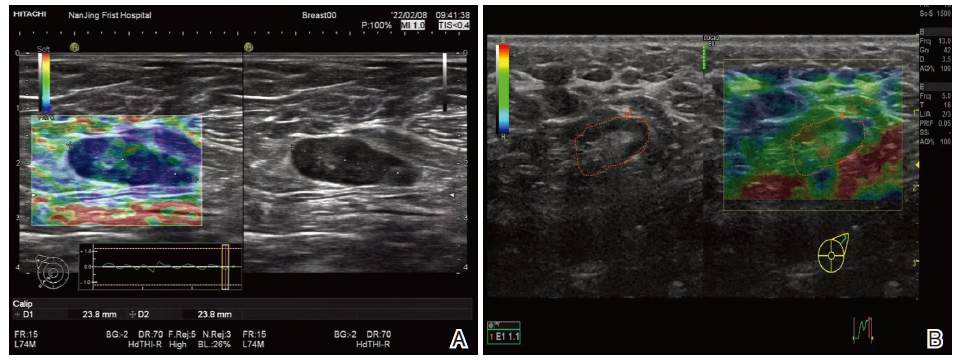

CDU检查显示, 良性结节组患者L/S比值明显高于恶性结节组(P< 0.05), 良性结节组患者CDFI血流特点以无血流型为主, 恶性结节组以门型为主(P< 0.05), 详见表1, 两组CDU图像见图1。

UE显示, 良性结节组患者评分以1~2分为主, 恶性结节组以3~4分为主(P< 0.05), 详见表2。两组UE图像见图2。